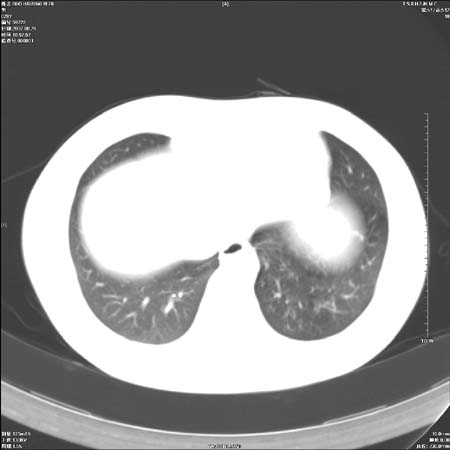

男性,28岁,体检发现左肺病变,患者只有背部隐痛感,哀哉,真不忍心下诊断啊。

左肺肺门区肿块影,分叶明显:诊断肺癌应该没有疑问。

鉴别:中央型肺癌-肿块那么明显一般合并节段肺不张或阻塞性炎症。

肺癌可能性大。(有分叶,毛刺)

左侧肺门区见一块状病灶可见分叶,纵隔内及左肺门见肿大淋巴结,应该是周围型肺癌而不是中心型肺癌,原因有以下2点,1未见阻塞肺气肿和阻塞性炎症,这么大肿块如果是中心型肺癌就是未分化型或小细胞型肺癌不出现阻塞性肺不张也应该有阻塞炎症或阻塞性肺气肿,2如果是中心型肺癌临床出现最早的症状是咳嗽(此时可无任何异常影象),而此人这么大肿块只有背部隐痛是体检才发现无法解释.

左肺门区分叶状软组织肿块,纵隔内有肿大淋巴结,诊断肺癌应该问题不大。

直接下肺癌诊断还太早,病灶较大,估计5cm以上,但阻塞性改变及对临近纵隔及支气管侵犯不明显,密度较均匀,弓旁见一单个淋巴结,需要排除炎症性肿块及腺瘤,平滑肌瘤等。